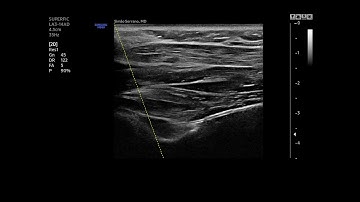

Suprascapular nerve block (Meier approach)